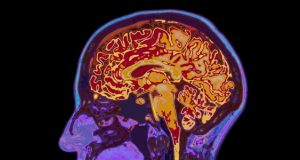

Otak mengungkapkan pilihan sebelum kita menyadarinya, demikian temuan studi

Sebuah studi menunjukkan bahwa kita tidak memiliki kebebasan dalam mengendalikan atas pilihan pribadi kita sendiri daripada yang telah kita pikirkan, dan bahwa aktivitas otak...